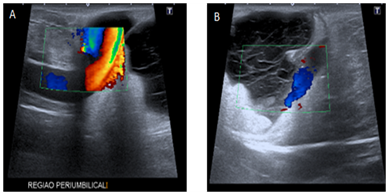

MRI performed 04 months after the CT scan shows signs of chronic liver disease with juxtaposing hepatic nodules with peripheral enhancement, associated to satellite nodules and splenomegaly; increased caliber of portal, splenic and superior mesenteric veins, with recanalization of paraumbilical vein, inferring portal hypertension (Figure 1).

Figure 1 In A, Axial CT scans with contrast and in B, MRI without contrast in the axial T2 plane shows recanalization of paraumbilical vein insinuating through the umbilical hernia.